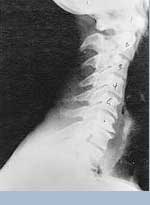

Phase two subluxation degeneration is normally seen in subluxations that have been present between 20 and 40 years. This phase has some of the same characteristics of the previous phase including a loss of normal curvature and position as well as an alteration in segmental motion. In addition, spines with Phase Two Subluxation Degeneration many times show a reduction in the patient's range of motion in that area. X-rays of a phase two begin to show calcium changes or buildup at certain levels of the spine. These changes are sometimes called by many names including spurs and arthritis. Disc spaces between the affected vertebrae are noticeably narrower and may appear to be flattening out. Although most people with Phase Two Subluxation Degeneration may not exhibit any symptoms, some may start to feel stiff or achy. Chiropractic reconstructive care for patients in phase two ranges from 1.5 years to 2.5 years. Again, if Phase Two Subluxation Degeneration is left uncorrected it slowly advances to the next phase.